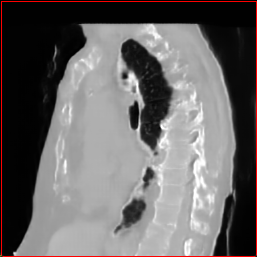

Figure 2: Qualitative comparison across axial (top row), sagittal (middle row), and coronal (bottom row) views. Columns correspond to different methods. MAISI-DDPM and MAISI-v2 in this figure are unconditional synthesis which do not use ControlNet or segmentation maps.

Qualitative Evaluation:

Figure 2 presents representative slices from the axial, sagittal, and coronal planes. GenerateCT (Hamamci et al. 2024) is a 2D model, so it lacks inter-slice consistency, leading to poor image quality in the sagittal and coronal views. MedSyn (Xu et al. 2024) produces noticeably blurry results with mosaic-like artifacts, such as region inside the red box. HA-GAN (Sun et al. 2022) generates visually sharp images but with mosaic-like artifacts, such as region inside the red box. Also, its voxel spacing is not available, which limits its applicability in real-world medical imaging tasks. Moreover, all three methods are restricted to synthesizing small anatomical regions. In contrast, both MAISI and MAISI-v2 are capable of generating high-quality 3D volumes that span larger body regions while preserving fine anatomical details and realistic structure.